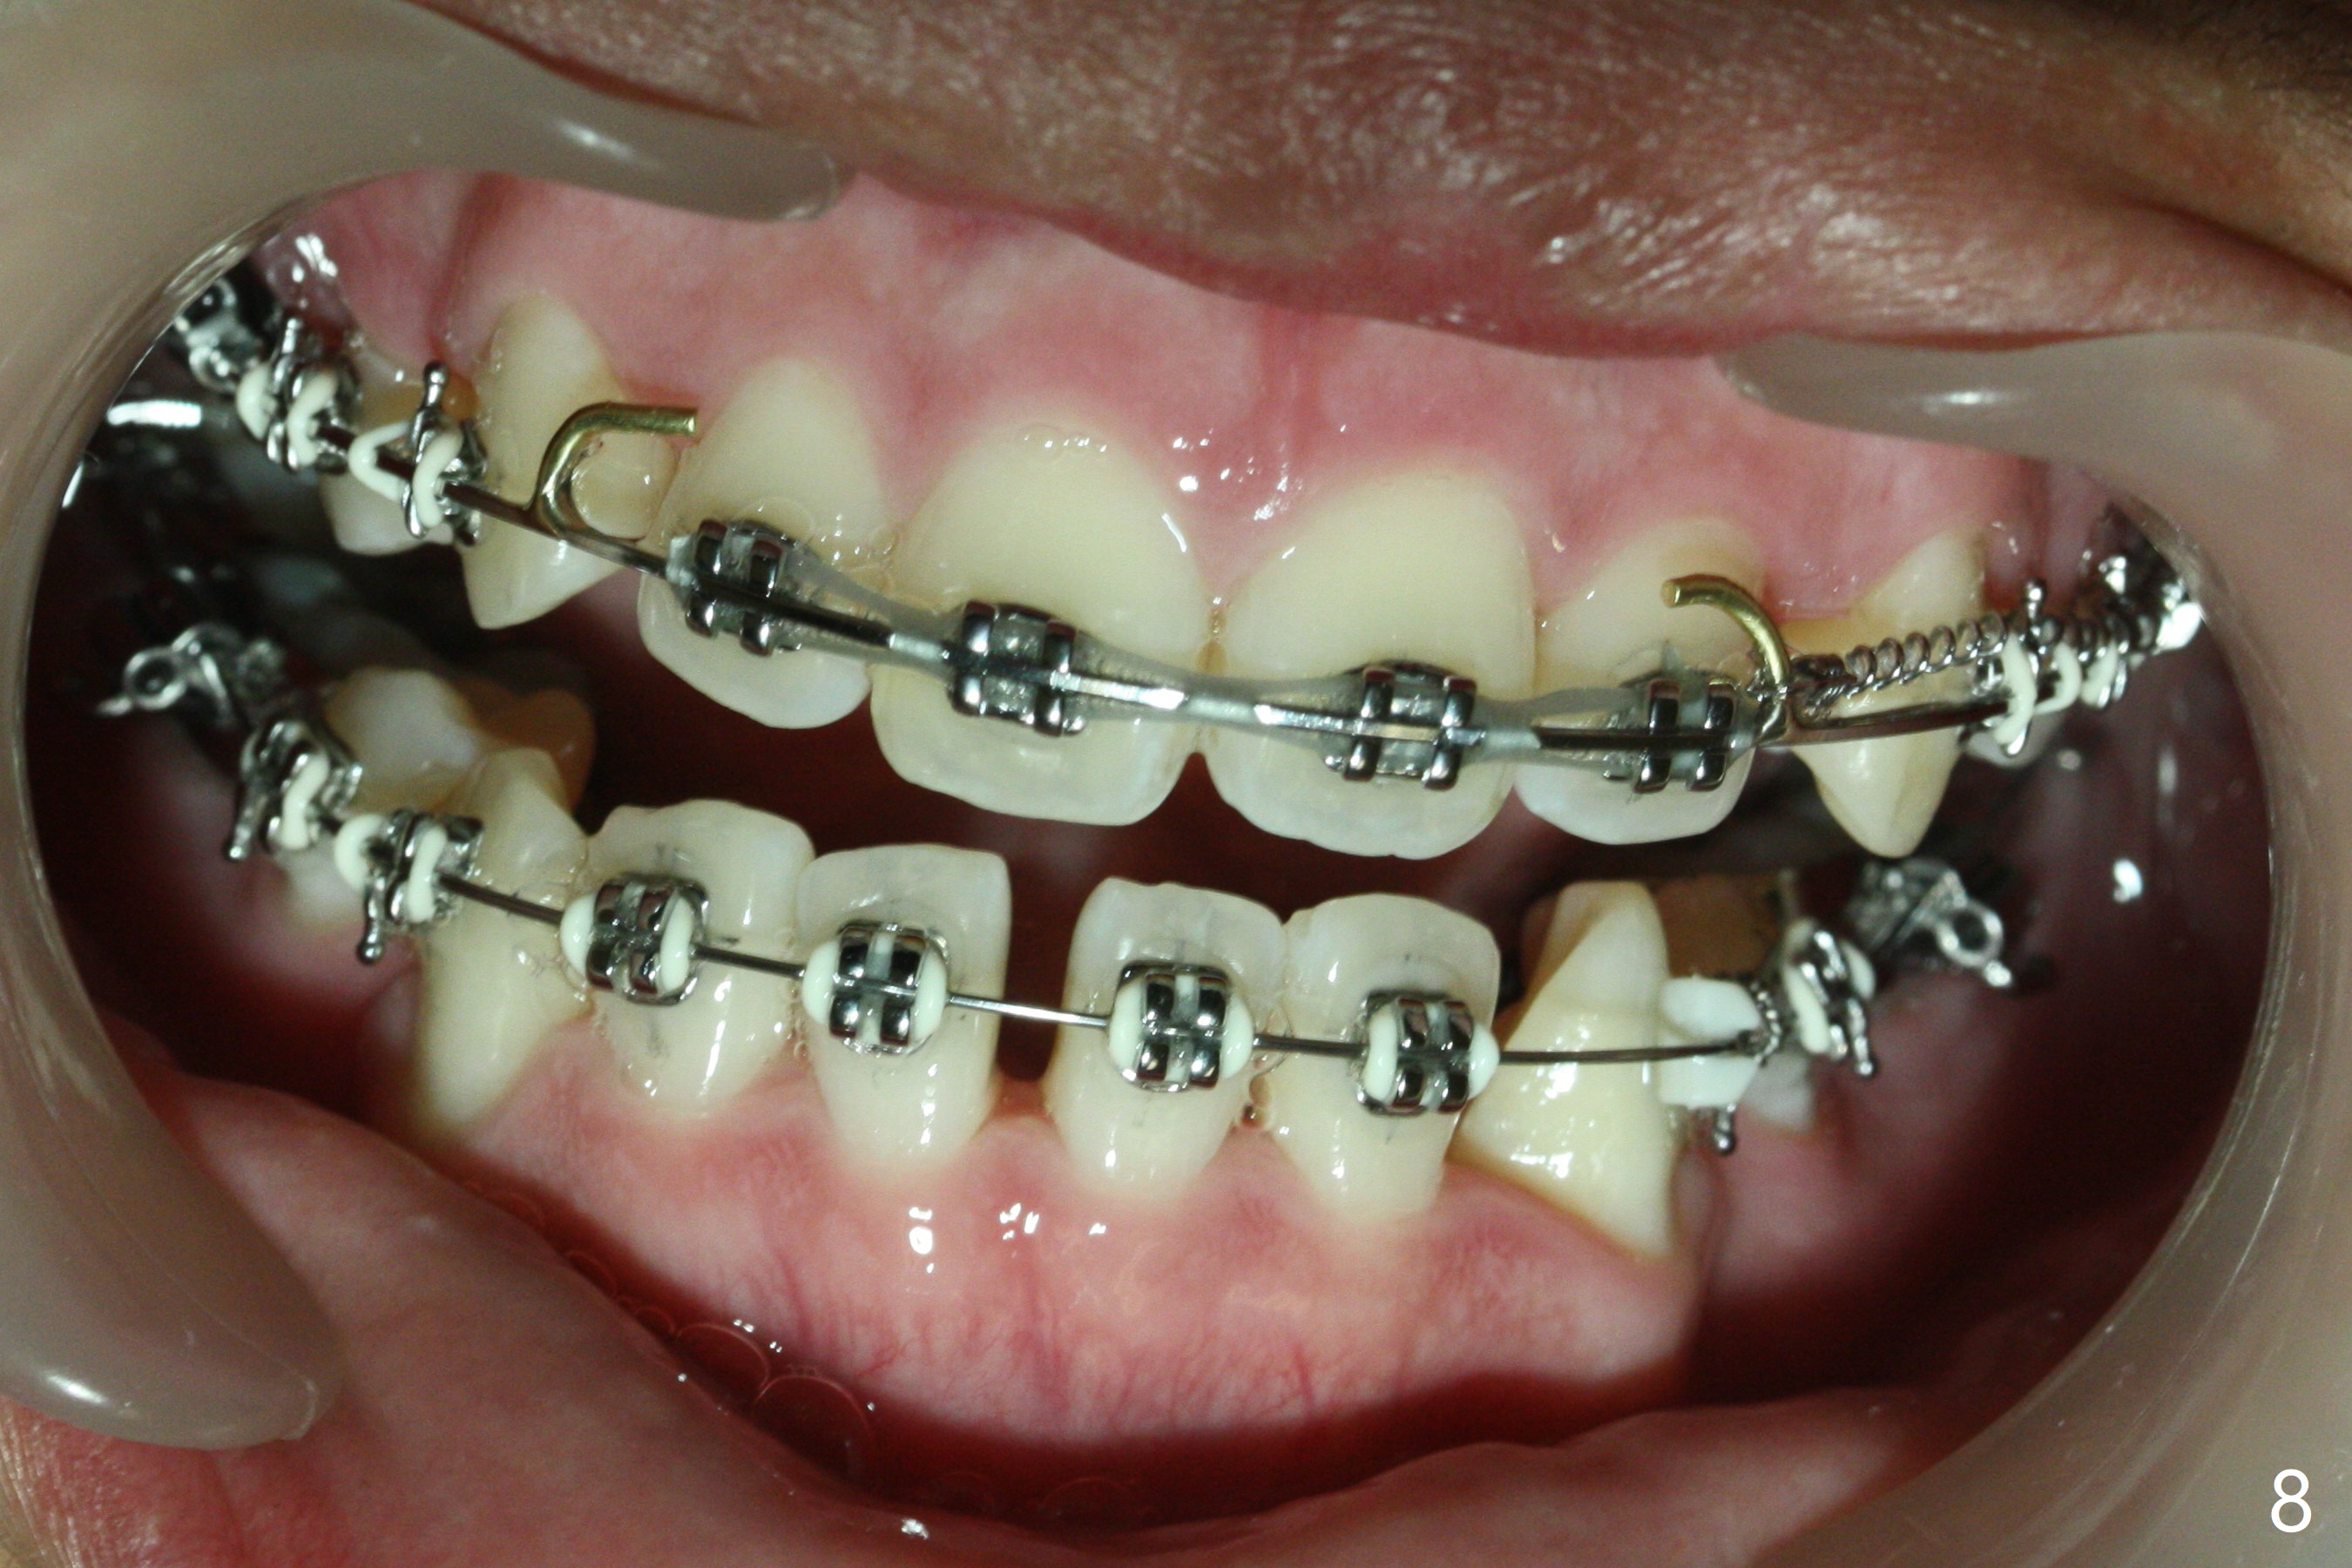

Twelve months post extraction and banding, there is anterior overjet. A posted wire is used to retract the upper incisors for a month. It appears that the upper midline deviates to the right (Fig.6, as compared to Fig.5 (pre-treatment)). Closed coil spring is removed on the right in hope that the upper midline will shift to the normal by the left coil spring (Fig.7-9). Is there a better alternative? There is mild root tip resorption 2 years 1 month post banding/immediate post debanding, as related to extraction ortho (Fig.10).